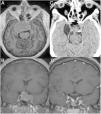

Cavernous sinus (CS) invasion is found in 15–20% of pituitary adenomas; it represents a poor prognosis factor and a surgical challenge even in experienced pituitary centers. We present our experience and technical note description for surgical management of pituitary adenomas with CS invasion in acromegaly by the transsellar lateral approach with an endoscopic endonasal transsphenoidal route.

ResultsThirty-two of 94 patients with diagnosis of pituitary adenoma treated at our institutions (34%) had acromegaly; thirteen of patients with acromegaly diagnosis met the inclusion criteria for CS invasion. Postoperative images reported gross total resection in 10 patients (76.9%). Mean follow-up time was 28.3 months. Remission criteria were achieved in nine patients (69.2%), with one of these patients (11.1%) having recurrence during follow up. All patients with no biochemical remission had improvement in GH and IGF profiles. Three patients without remission underwent radiosurgery (14Gy), and one patient had remission after the procedure.

ConclusionsWe consider this to be a safe and efficient approach for tumors invading CS, when surgical team have good experience in endoscopy of the skull base and reconstruction techniques, appropriate instruments are available, and tumor has soft consistency.